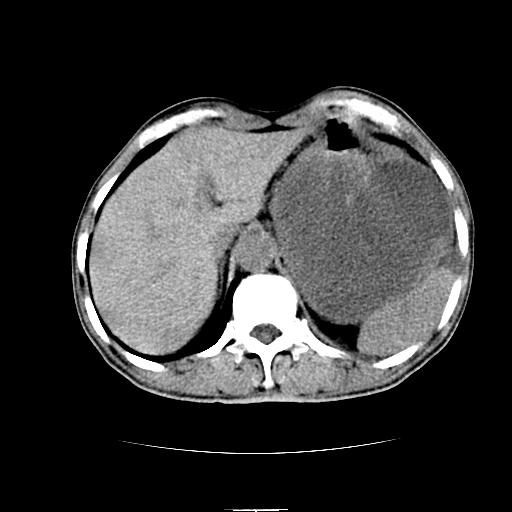

胰尾部巨大囊性病变,胰腺体积增大.左肾吉氏筋膜增厚.1慢性胰腺炎伴随假性囊肿2左肾囊肿

左上腹胃、脾及胰腺间巨大囊性占位性病变,内见多数薄隔,有轻度强化,明显占位效应,胰腺及左肾结构清楚,明显向后下方推压 移位。左肾见一小囊肿.多考虑:1 网膜巨大囊肿。2 左肾小囊肿。

1胃脾胰之间一巨大囊性影,胃明显向前推移,胰体尾部似肥大,考虑囊性影来源于胰腺(假性囊肿?)2左肾小囊肿。

左上腹囊性占位,虽与胰腺分界不清,胰尾似乎受压前移,病灶最大截面并不在胰腺水平,考虑来源于网膜可能性大吧,应再详细追问病史.

胃脾胰之间一巨大囊性影,内可见间隔,应为囊实性占位:多考虑:1 网膜巨囊腺瘤?。2 左肾小囊肿